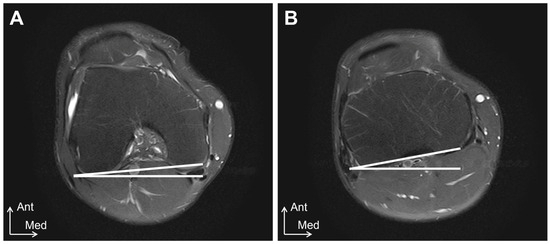

Relationship Between the Sagittal and Coronary Alignment of the Tibiofemoral Joint and the Medial Meniscus Extrusion in Knee Osteoarthritis

Background/Objectives: This study aims to clarify the reproducibility, validity, and accuracy of tibial external-rotation alignment evaluation using ultrasound imaging and to investigate the relationship between medial meniscus extrusion (MME) and tibiofemoral alignment in both the sagittal and coronal planes in knee osteoarthritis [...] Read more.

Background/Objectives: This study aims to clarify the reproducibility, validity, and accuracy of tibial external-rotation alignment evaluation using ultrasound imaging and to investigate the relationship between medial meniscus extrusion (MME) and tibiofemoral alignment in both the sagittal and coronal planes in knee osteoarthritis (OA). Methods: Study 1 included 10 healthy participants. The tibial external-rotation angle was calculated using MRI. In the ultrasound imaging evaluation, the differences in the distance from the most posterior points of the tibial and femoral condyles to the skin were calculated as the medial and lateral condyle gaps, respectively. The mediolateral (ML) gap was calculated by subtracting the lateral condyle gap from the medial condyle gap. Study 2 included 63 patients with unilateral OA and 16 healthy controls. MME was compared according to the severity of OA, the degree of tibial rotation, and the presence or absence of a tibial posterior shift. Results: Ultrasound imaging examinations showed high intra- and inter-rater reliabilities (0.786–0.979). The ML gap significantly affected the tibial external-rotation angle, determined using MRI. The ML gap of ultrasound imaging was significantly correlated with the ML gap of MRI. MME was significantly higher in the Early OA group than in the Control group. There was no significant difference in MME based on the tibial rotation degree. The group with a tibial posterior shift exhibited significantly more MME than that without a posterior shift. Conclusions: Ultrasound imaging is useful for evaluating knee alignment. MME was found to be associated with the tibial posterior shift. Full article